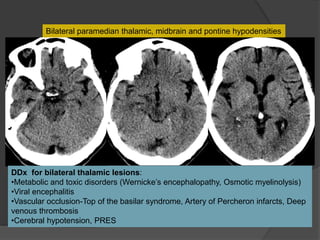

Bilateral paramedian thalamic, midbrain and pontine hypodensities

DDx for bilateral thalamic lesions:

•Metabolic and toxic disorders (Wernicke’s encephalopathy, Osmotic myelinolysis)

•Viral encephalitis

•Vascular occlusion-Top of the basilar syndrome, Artery of Percheron infarcts, Deep

venous thrombosis

•Cerebral hypotension, PRES

Acute infarcts in the pons, midbrain and bilateral thalami

“V sign”

Lazzaro N et al. AJNR Am J Neuroradiol 2010;31:1283-1289

•An uncommon anatomic variant: a single dominant

thalamoperforating artery supplies bilateral

paramedian thalami and the rostral midbrain

•Clinical diagnosis difficult

Case 2 Dx: Artery of Percheron Infarct

Most common etiology is cardioembolic

Additional small infarcts in the right MCA distribution